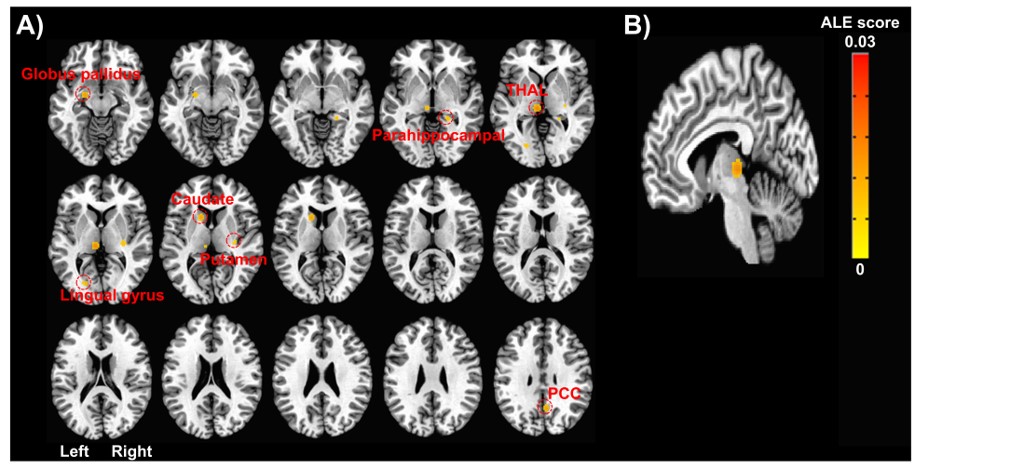

이를 위해 우선 만성 통증과 관련 기능적 뇌 영상법(functional MRI와 PET)을 활용한 연구 1572편을 검토하고, 이들 중 연구방법론에 적합한 75편을 대상으로 체계적 문헌 고찰 및 메타 분석 연구를 시행했다.

그 결과 만성 통증 치료 전후를 비교했을 때, 일차 감각 및 운동 피질과 시상 등의 부분에 대한 기능적 활성이 치료 후에 유의하게 감소하는 경향과 더불어 앞대상회피질(ACC), 뇌섬엽(insula)의 기능적 활성 또한 감소하는 경향이 있다는 것을 확인했다.

또한 이들의 대사 활동도 일차 감각 및 운동 피질과 시상, 그리고 뇌섬엽은 포도당 흡수와 혈류량 증가, 진통 효과와 관련이 있는 뮤(μ) 아편양 수용체 결합 전위가 유의하게 증가하는 것으로 나타났으며, 전대상회피질에서는 반대로 이들 대사 활성이 감소하는 경향으로 나타났다.

특히 이번 연구에서 만성 통증 치료에 가장 일관되게 기능적 활성이 변화하는 것으로 나타난 ‘시상’은 통증 전달 및 조절에 중추적인 역할을 하며, 시상 기능에 장해가 생기면 만성 통증 증상이 나타날 수도 있다는 것을 확인, 이 부위의 기능적 활성 감소 경향은 통증 자극을 더 이상 현저하게 느끼지 않는다는 것을 반영할 가능성이 있으며, 이는 만성 통증에 의해 과민해진 뇌의 통증 처리 활동이 치료에 의해 개선되었기 때문으로 분석했다.